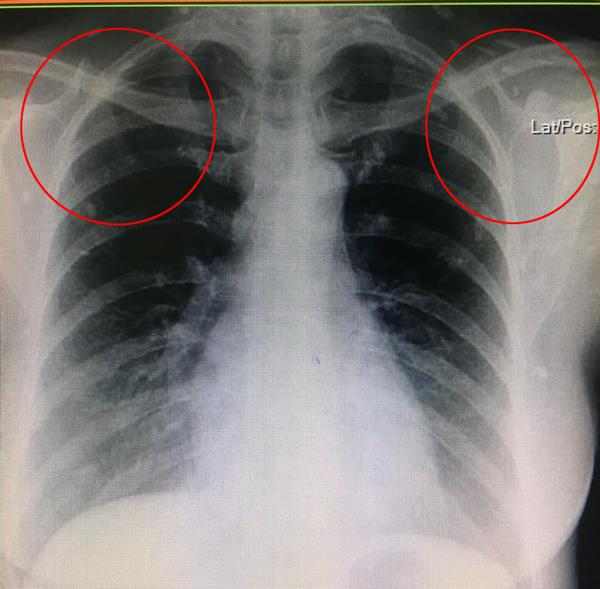

Gần đây một cư dân mạng Thái Lan đã gây xôn xao bằng 2 bức ảnh chụp X-quang khiến bất cứ ai cũng phải giật mình kinh hãi.

Theo như bài viết chia sẻ thì một người phụ nữ thường ăn thịt lợn tái, chưa chín khiến cơ thể cô bị xâm chiếm bởi hàng trăm ký sinh trùng. Trước đó, người phụ nữ cảm thấy cơ thể đột nhiên mệt mỏi bất thường và khó thở nên đã tới bệnh viện khám.

Sau khi chụp X-quang, thấy khắp cơ thể đặc biệt đầy những đốm trắng lạ kỳ. Bác sĩ khi nhìn vào cũng vô cùng kinh ngạc và cho biết đây là những ký sinh trùng đang nằm trên khắp cơ thể nữ bệnh nhân, đặc biệt là phần chân.

Bác sĩ cũng cảnh báo nếu toàn bộ ký sinh trùng này không được loại bỏ thì chỉ một thời gian ngắn nữa, nó có thể gây suy hô hấp hoặc thậm chí tử vong.

Loại ký sinh trùng này được xác định là ấu trùng của sán dải heo hay sán dải lợn. Những nang ấu trùng nhiễm vào não, cơ hoặc các mô khác có thể gây ra các cơn động kinh khởi phát tuổi trưởng thành.